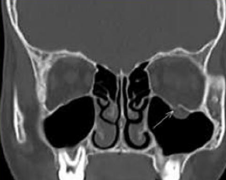

New cards

medial

Which wall of the orbit is roughly rectangular in shape?

16

15 mm behind the margin

Where is the widest point of the orbit? (Hint: NOT at margin)

84

B

The most common site for a blow-out fracture following trauma involves which of the following orbital bones?

A. zygomatic

B. maxillary

C. ethmoid

D. lacrimal

E. sphenoid

F. frontal

G. palatine